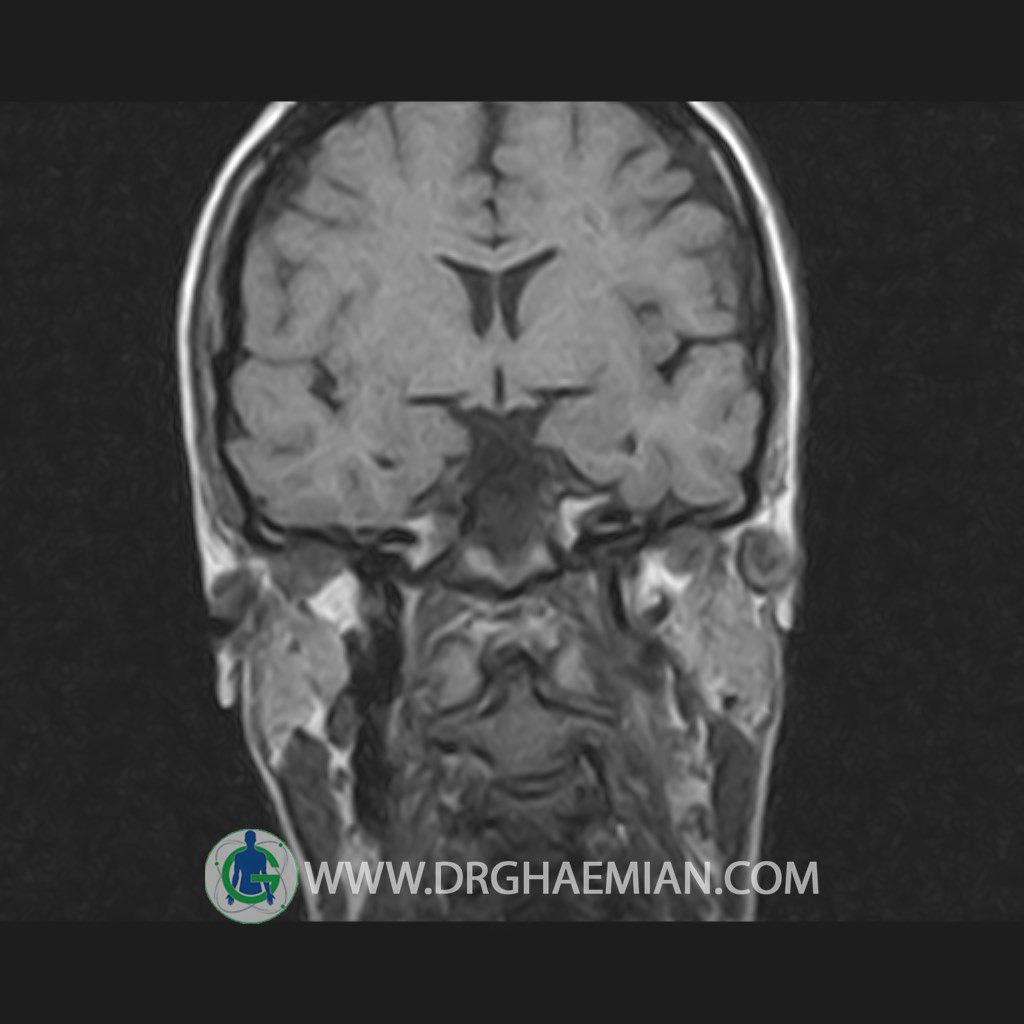

پزشکان اغلب از تصویربرداری ام آر آی برای تشخیص و درمان عارضه های پزشکی که فقط با استفاده از اشعه ایکس یا میدان مغناطیسی و امواج رادیویی قابل مشاهده است، استفاده می کنند. دستگاه ام آر آی تصاویر دقیق از ساختار های داخلی بدن ایجاد می کند. در این کیس هیپرپلازی هیپوفیز و آدنوم مشاهده می شود.

HYPOPHYSIS MRI

(with and without contrast)

Technique: Axial , coronal T1 , Axial , coronal , sagittal T2 , Axial, coronal T1 post Gd & 64 dynamic thin coronal slices.

REPORT :

The sella shows normal size , position and configuration .

The borders of its floor and walls are smooth and sharply defined .

The infundibulum is centered and of normal size .

The optic chiasm and suprasellar spaces appear normal .

The cavernous sinus and imaged portions of the internal carotid artery and carotid siphon are unremarkable .

Evaluable portions of the neurocranium show no abnormalities .

The sphenoid sinus is clear and pneumatized .

– Mild convexity at superior border of pituitary gland with post contrast homogeneous enhancement suggestive for pituitary hyperplasia & iso signal adenoma

is seen